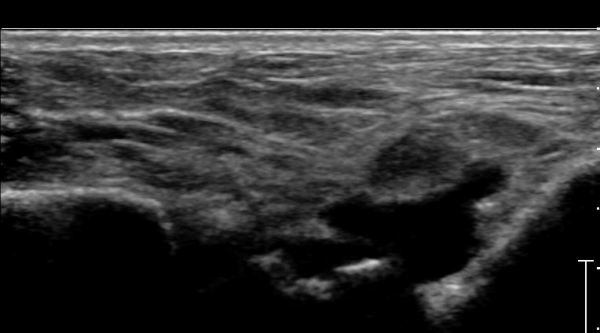

Àü°ÅºñÀδë Á¾´Ü¸é°Ë»ç»ó Àü°ÅºñÀδëÀÇ Àú¿¡ÄÚ À§Ãà°ú Á·±Ùµ¿(sinus tarsi) ¼ö¾×Àú·ù°¡

°üÂûµÈ´Ù(»çÁø 2, 3).